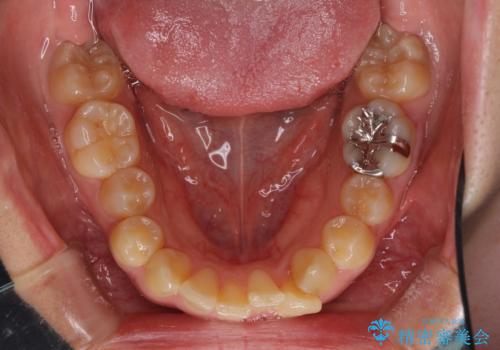

八重歯の抜歯矯正 補助装置を用いたインビザライン矯正

- 下の前歯のデコボコを気にして来院された患者様です。

来院当初、上顎の八重歯は気にしていらっしゃらなかったのですが、矯正治療をするのであれば、しっかりと治した方が良いと説明し、全顎矯正を行うこととしました。

八重歯の移動量が多く、インビザライン単体での治療は困難と判断し、補助装置により八重歯移動後にインビザラインを用いることとしました。